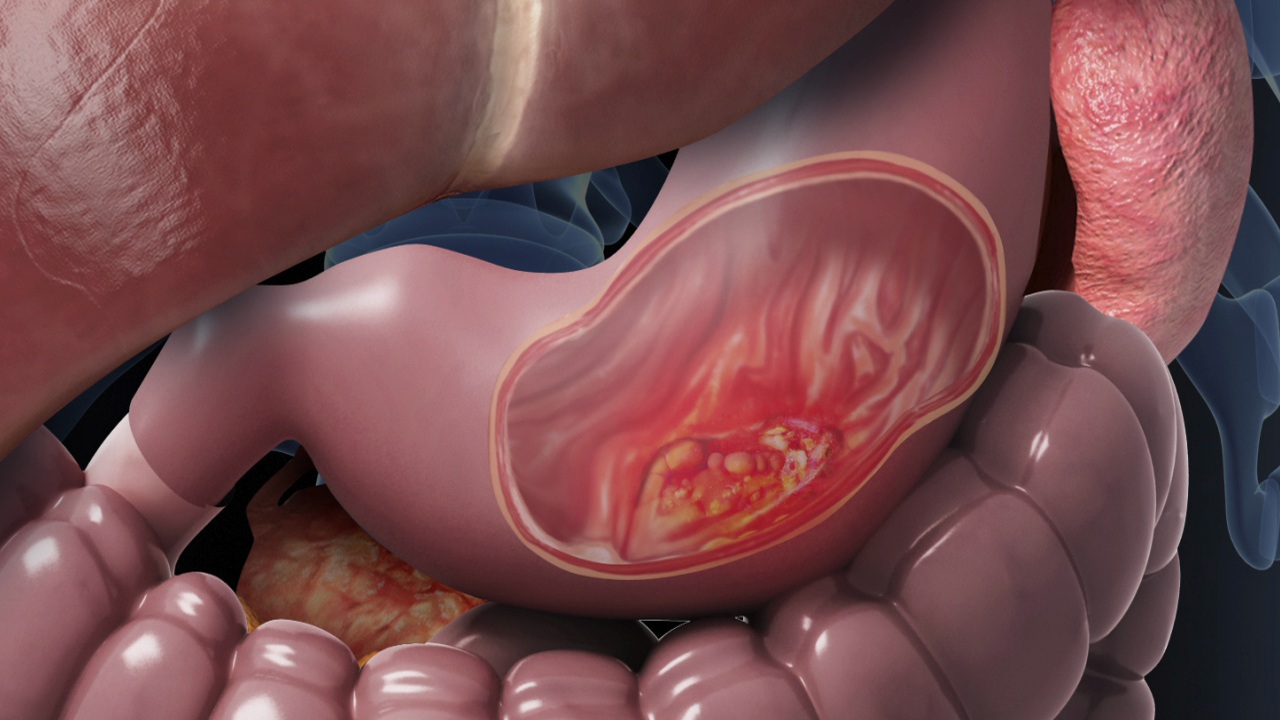

Gastrointestinal Cancer

Gastrointestinal cancer refers to malignant conditions of the gastrointestinal tract (GI tract) and accessory organs of digestion, including the esophagus cancer, stomach cancer, biliary system, pancreas, small intestine cancer, large intestine cancer, rectum and anus

It can be used after surgery to kill any cancer cells that might remain. It can also be used before the surgery to shrink a large cancer so that it becomes easier to remove during surgery. For patients with advanced stage of cancer, radiation therapy might help to ease the pain and relieve some symptoms.